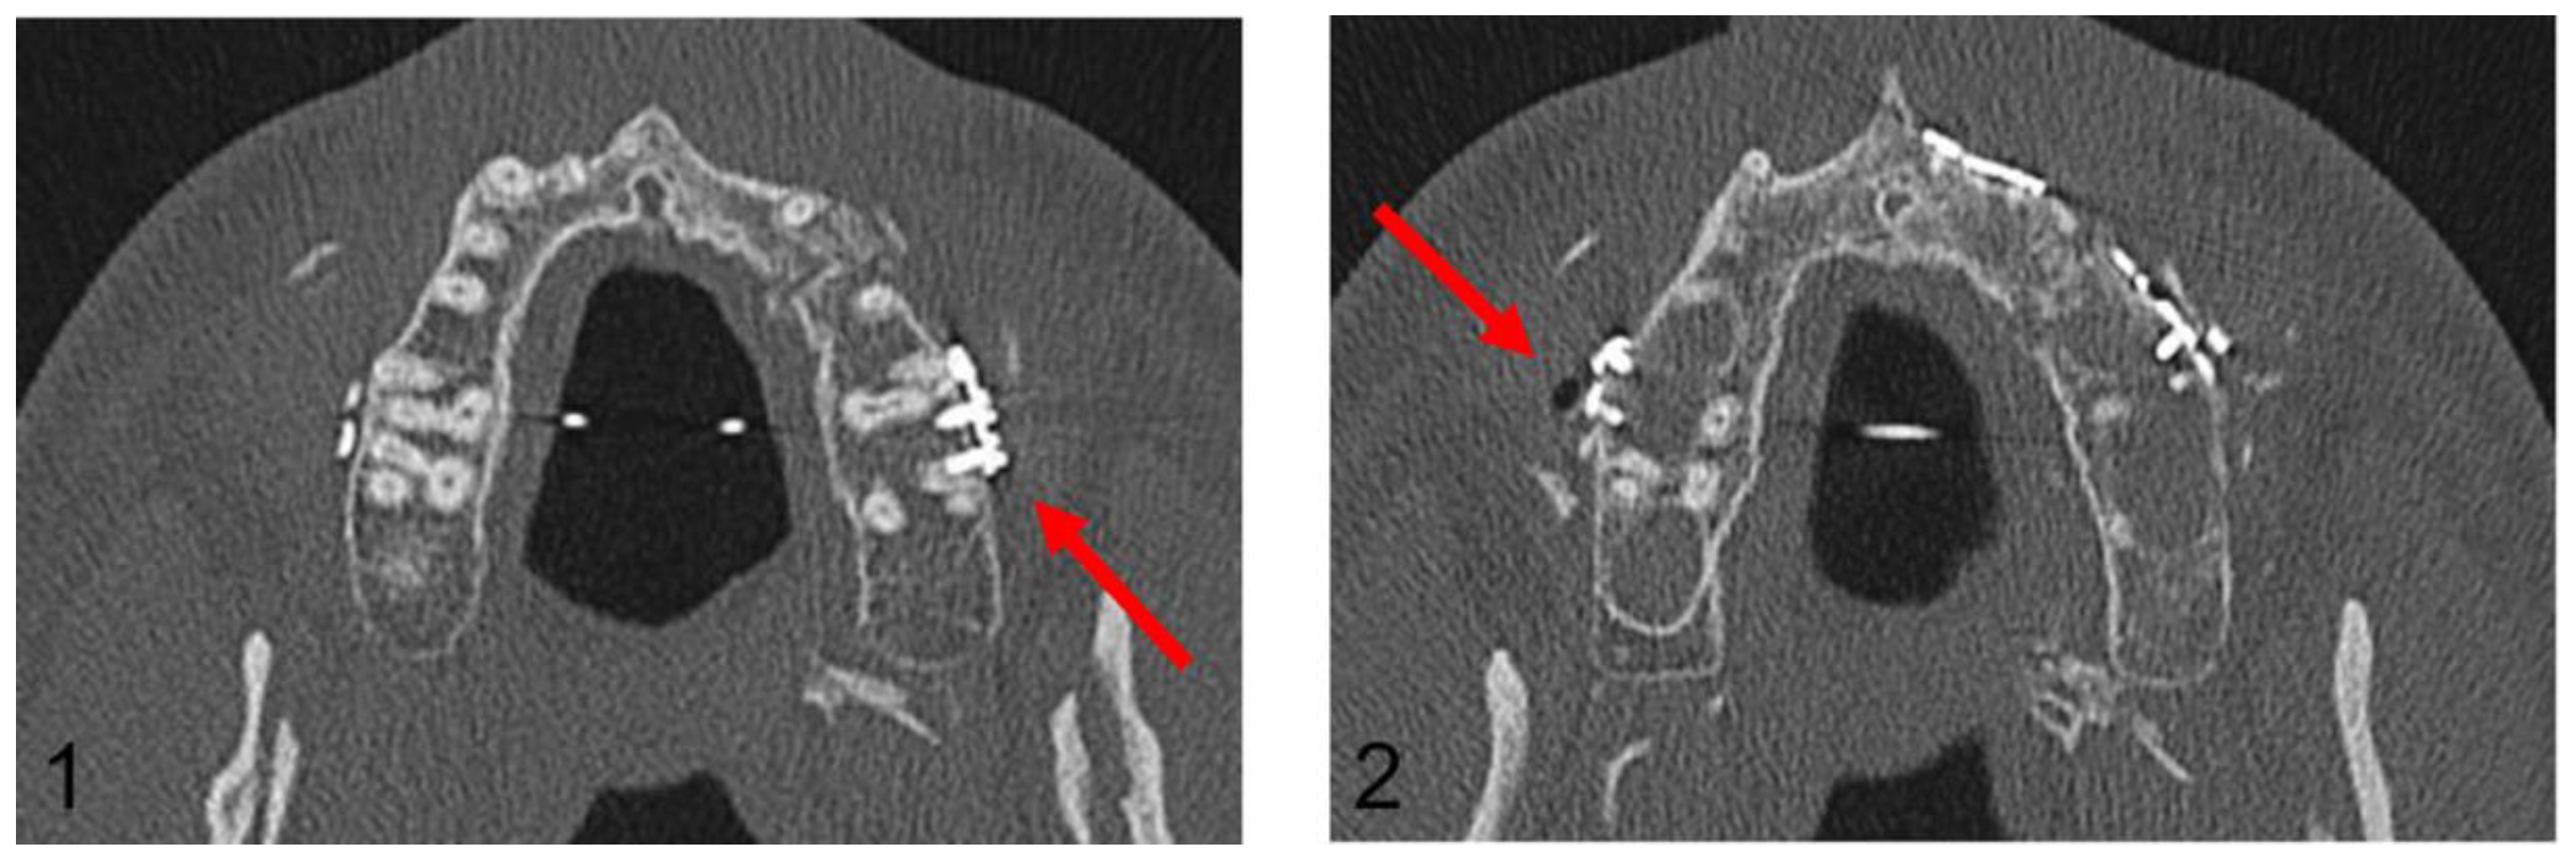

Figure 7.

Axial plane of post-operative CT scan. Image (1) shows an injury of the mesiobuccal tooth root of tooth 27, while in image (2), no root injury in the right maxillary molars is detected (red arrows).

In the Maxilla Conventional cohort, 94 radiological projections of osteosynthesis screws with the dental roots were detected in the post-operative OPG. In contrast, post-operative CT imaging detected only 10 dental root injuries. In the Maxilla PSI cohort, 64 radiological projections were detected; however, no dental root injury could be detected in post-operative CT imaging. In the mandible, a total of 106 projections in the premolar and molar region were recorded in the post-operative OPG, but only 12 root lesions were detected in post-operative CT scan.